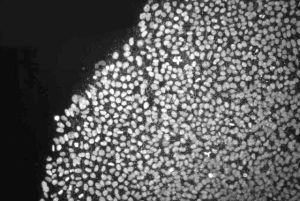

萬能細胞萬能細胞,美國和日本的研究小組宣布成功把普通的人體皮膚細胞轉化為了具備胚胎幹細胞功能的新型“萬能細胞”,是從人體中提取了一種名為“纖維原細胞”的皮膚細胞,然後向其中植入4種新基因,從而製造出一種名為IPS的細胞,它具有類似胚胎幹細胞的功能,能夠最終培育成人體組織或器官,這一被學界稱為生物科學“里程碑”的重大突破,有望幫助科學家繞過克隆技術的倫理、道德紛爭,為醫學套用打開大門。

3、得出的實驗結果一樣——他們都成功地將普通人體皮膚細胞改造成了幹細胞。從理論上說這種幹細胞的功能類似通過胚胎克隆技術取得的胚胎幹細胞,能夠最終培育成人體組織或器官。由於這種幹細胞能通過基因組合控制,因此有“萬能細胞”、“變色龍細胞”之稱。

萬能細胞1、萬能細胞與普通細胞相比具有兩大優勢:其一可以在體外無限繁殖,這對於有限的細胞資源來說非常有吸引力。其二可以轉化成任何需要的體細胞。我們平時遇到的很多疾病,例如脊椎損傷、老年痴呆症、帕金森氏症、神經性損傷病、糖尿病、心臟病、不孕症等,可能會由於組織細胞已經死亡而無法治癒,但是當我們可以通過萬能細胞轉化為需要的組織細胞、替代死亡的細胞時,這些疾病就有希望得以治療,所以萬能細胞的臨床意義極大。目前研究的新型萬能細胞可以從病人的血液、皮膚、頭髮細胞中提取,解決了之前胚胎幹細胞的兩大問題:一是新型萬能細胞來自病人自身,所以不存在免疫排斥問題;二是新型萬能細胞不會破壞胚胎,因此不存在來源的倫理問題。